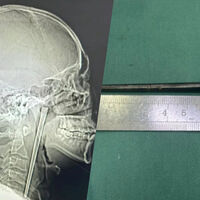

В китайском городе Далянь 46-летнего мужчину срочно доставили в больницу с сильной болью в горле. Во время обследования врачи нашли в его горле металлическую палочку длиной около 12 сантиметров, с которой пациент прожил восемь лет, пишет Mothership.

Обследование показало, что металлическая палочка застряла в задней части горла, при этом около трех сантиметров предмета выступали вверх. Несмотря на длительное пребывание инородного тела, врачи не обнаружили значительных кровотечений или язв.

Медики провели минимально инвазивную операцию и смогли извлечь палочку через рот, не прибегая к разрезу шеи.